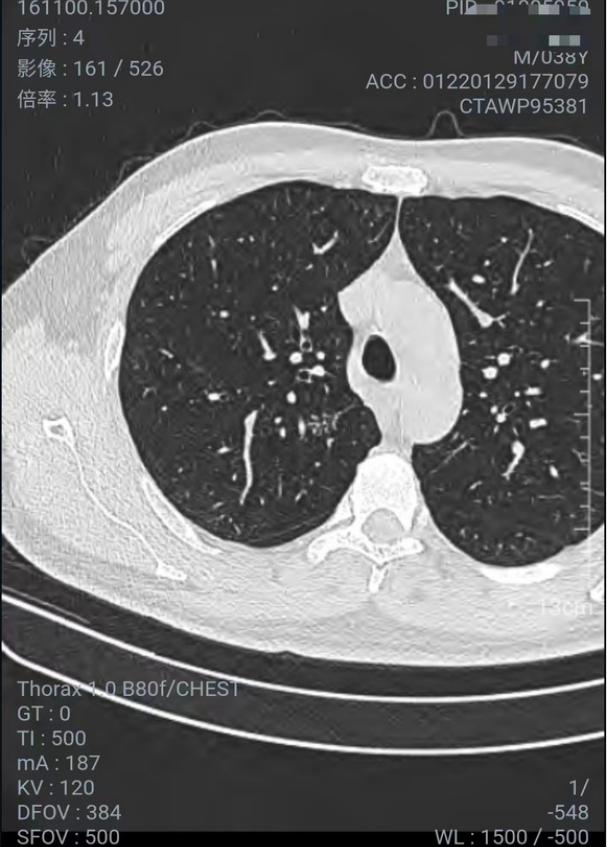

两侧胸廓对称;双肺野支气管血管束清晰,走行自然。双侧肺门不大。心影及大血管形态正常。纵隔内未见肿块及明显肿大淋巴结。右肺上叶后段亚实性结节状影,边缘不规则(Se4Im89),直径约8mm。右肺下叶钙化灶(Se4Im187)。右肺中叶叶间胸膜下斑索状影,边缘较清晰(Se4Im230),直径约3mm。(2021年12月体检发现)

2022年1月29日首次去A医院复查,40天后长大了,直径1.2cm了,不知道是体检机构有误差,还是确实长大了,看了医生说可能是炎症,开了半个月的消炎药(左氧氟沙星片+头孢地尼分散片),2022.2.18-3.4 期间服药。

这A医院可以在微信公众号上看到CT结果, 截图如下(不知道截的对不对)